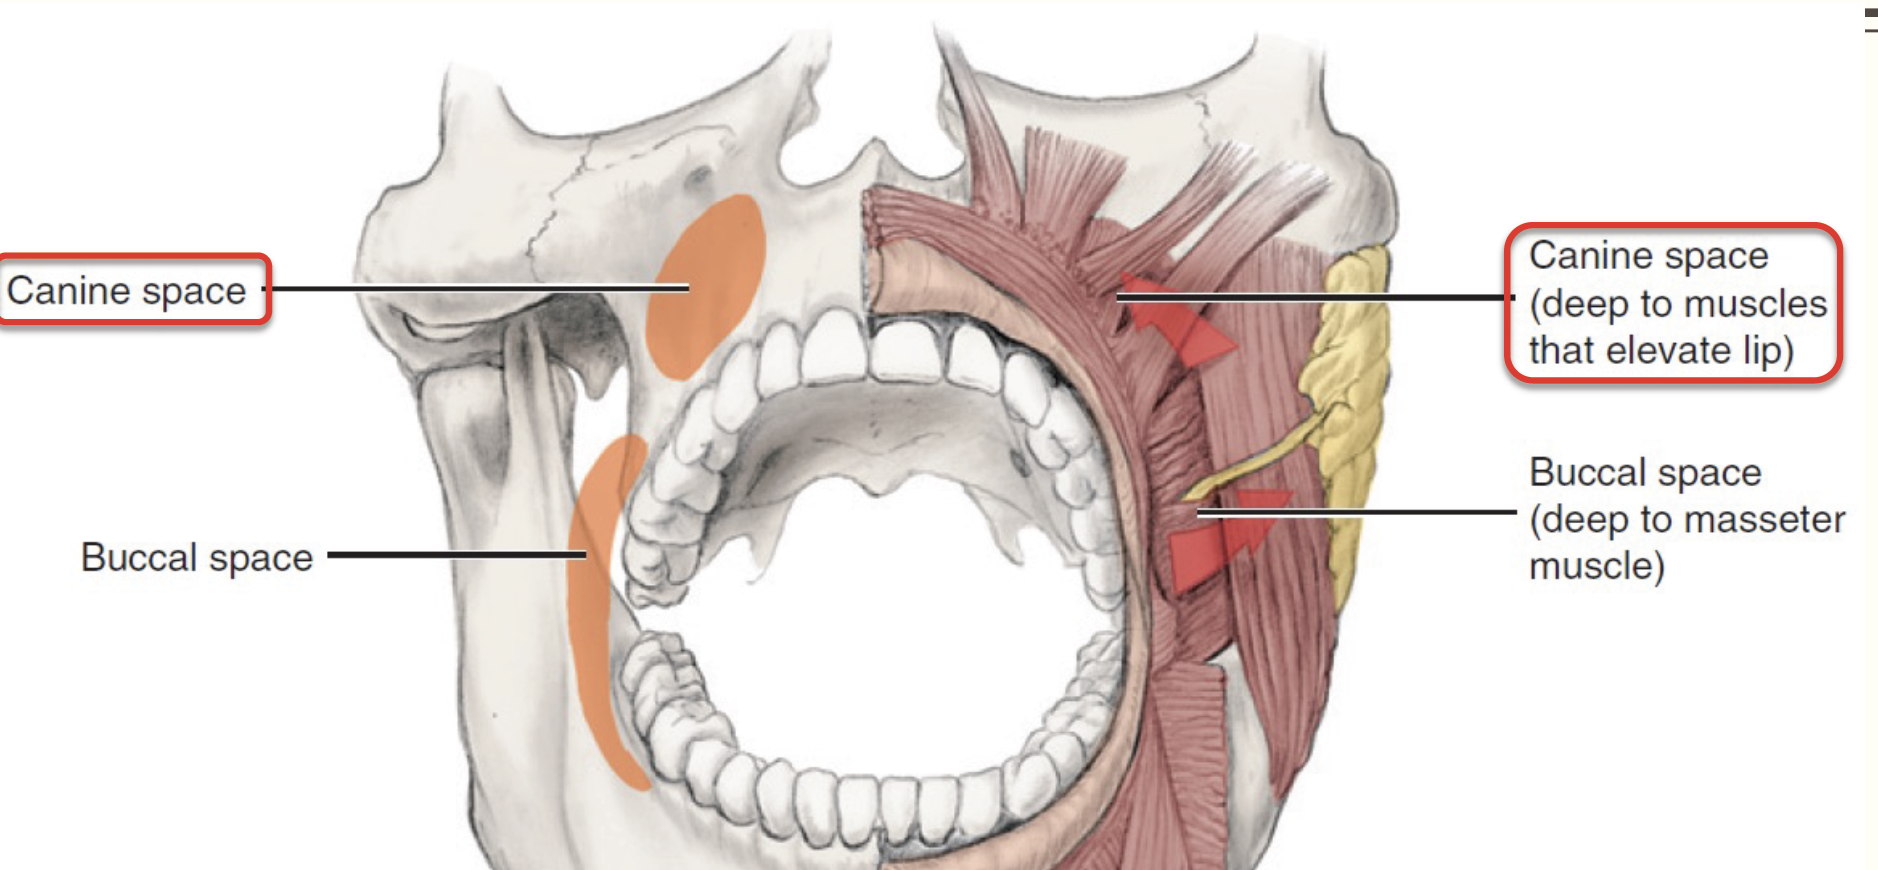

Canine space (Maxilla)

- Nasolabial sulcus

Buccal space

- Buccal fat pad

- Parotid duct

- Facial a.